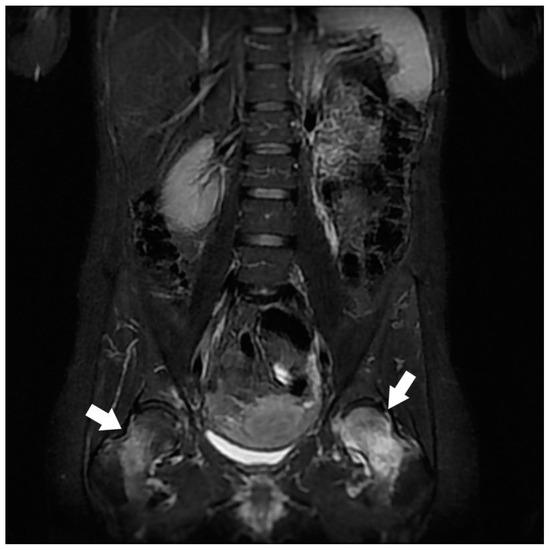

| Gluteal Muscles | Gluteal tendinobursitis | 21 |

| Musculotendinous | Gluteal tendinobursitis 2 | 10 |

| Osteoarticular | Congestive hip osteoarthritis 2 | 8 |

| Congestive degenerative sacroiliac arthropathy 2 | 8 | |